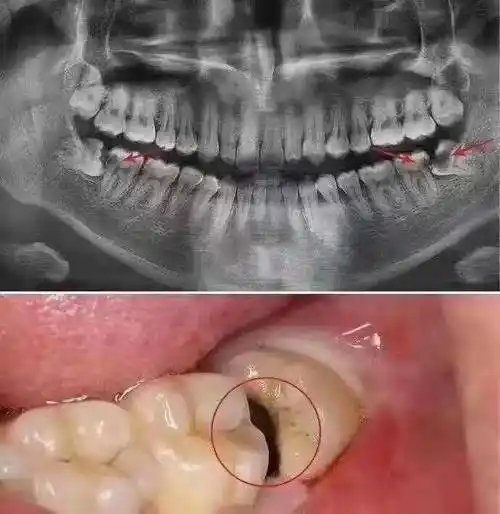

智齿_时候_酒窝